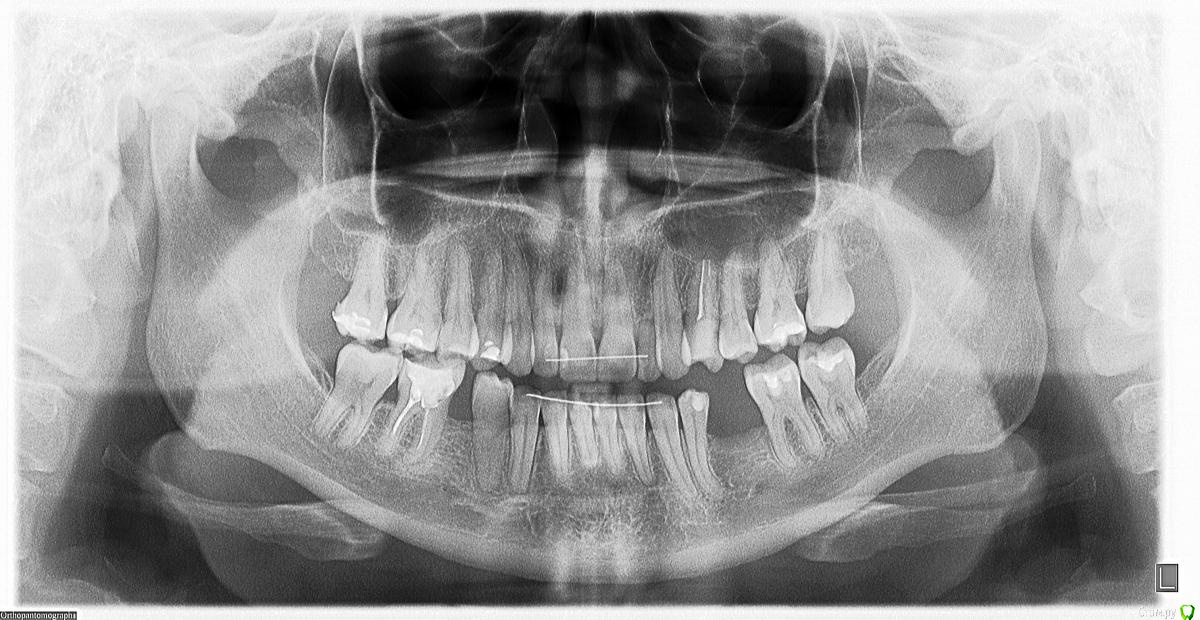

Девушка_пациентка Опубликовано 19 февраля, 2015 Поделиться Опубликовано 19 февраля, 2015 Добрый день, уважаемые профессионалы!У меня довольно сложный случай, как мне говорят. Хотелось бы услышать ваши комментарии и советы по поводу стратегии лечения/протезирования.Мне 36 лет. На нижней челюсти есть отсутствующие зубы. Дело в том, что их и не было никогда. Я не помню, чтобы мне когда-либо что-либо удаляли. Позабыть этого факта я бы не могла. Судя по смнимку стоматологи в нашем городе, у кого я была на консультации, утверждают, что состояние моей костной ткани - на 50-летний возраст. При этом у меня нет воспалительного процесса и кровоточивости десен. (Ретейнеры стоят из-за ортодонтического лечения, которое я проходила в 2010-2011 годах, исправляли клык на верхней челюсти). Тем не менее, десна у коренных зубов оседает, оголяя все больше их корни. Вопрос о мостах не стоит, т.к. опорные зубы не выдержат скорее всего такой нагрузки. Что касается имплантации, то в сентябре 2014 года мне была выполнена подсадка костной ткани внизу слева. Полгода я пила припараты кальция: Остеогеноно и Остеокомплекс. На контрольном снимке через 6 мес. (на мой дилетантский взгляд) ситуация стала выглядет еще хуже... Врач порекомендовал мне пить кальций еще как минимум год. А пока поменять пломбы в нижних зубах и один из них (с сильно оголившимся корнем) депульпировать.У меня ложилось впечатление, что он просто "умыл руки" и отправил меня по добру по здорову. Видимо, случай действительно сложный и он просто не хочет браться за него. А сказать об этом прямо почему-то не решился. Хотя, я могу ошибаться. Прошу ваших рекомендаций и прогноза.Показана ли имплантация в таких случаях, как мой? Каковы прогнозы? P.S. Диабетом, ревматизмом и пр. не страдаю. После родов в 2012 году было некоторое время нарушение кальциево-фосфорного обмена. Сейчас по анализам - норма. В анамнезе гопотериоз, но с 2008 года - стойкая ремиссия, не требующая приема препаратов. Гормоны с 2008 года контролирую каждые 3 месяца, - все в норме. В ближайшие полгода планирую вторую беременность. Хотелось бы только привести в порядок зубы перед этим. Стоит ли заниматься имплантацией сейчас или, в таком случае, целесообразнее отложить ее на более позднее время, а сейчас просто вылечить зубы (нижние коренные требуют замены пломб) и продолжать пить кальций? Прикрепляю снимки:1) Состояние на 04.09.2014 (перед подсадкой костной ткани слева с целью последующей имплантации)2) Состояние на февраль 2015 года (спустя 6 мес. после подсадки). Ссылка на комментарий

diesel87 Опубликовано 19 февраля, 2015 Поделиться Опубликовано 19 февраля, 2015 Здравствуйте, не ждите от препаратов кальция чуда или улучшения состояния кости, состояние через пол года возможно по высоте кости стало чуть хуже, но не критично. Грамотный специалист уже бы давно вам провел операцию имплантации в область нижнего левого отсутствующего зуба, совместно/без наращивании кости. Ссылка на комментарий